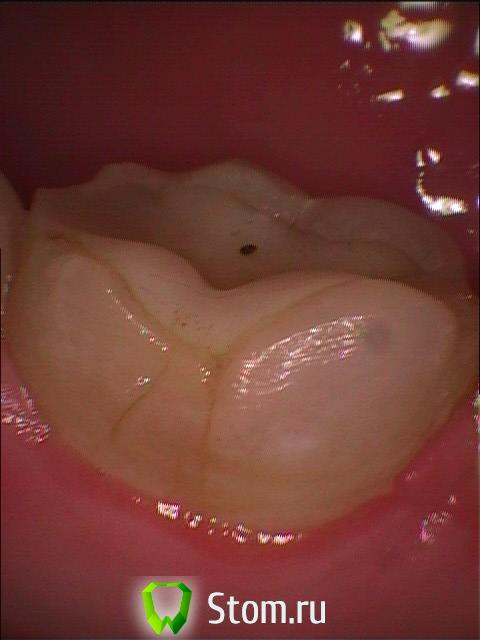

b737

4.01.12 г. пролечили 37 по жевательной и 36 на контакте с 37 в результате боли в обоих зубах на ходное, проходит за 3-5- макс. 15 сек после снятия раздражителя. и во время жевания, когда убираю давление, сразу дергает и проходит. (проблема есть в обеих зубах). в спокойном состоянии болей вообще нет. врач работал без коффердама, на оба зуба прокладка, кажется, СИЦ.

3. Обнаружил трещину в 36, рассматривается вкладка в 36, также предлагает ждать еще неделю, пломбировать временно по очереди и думать дальше - постоянно или депульпация.

post-23739-0-33784700-1326394992_thumb.jpg

post-23739-0-96211000-1326395001_thumb.jpg

post-23739-0-00513000-1326395422_thumb.jpg